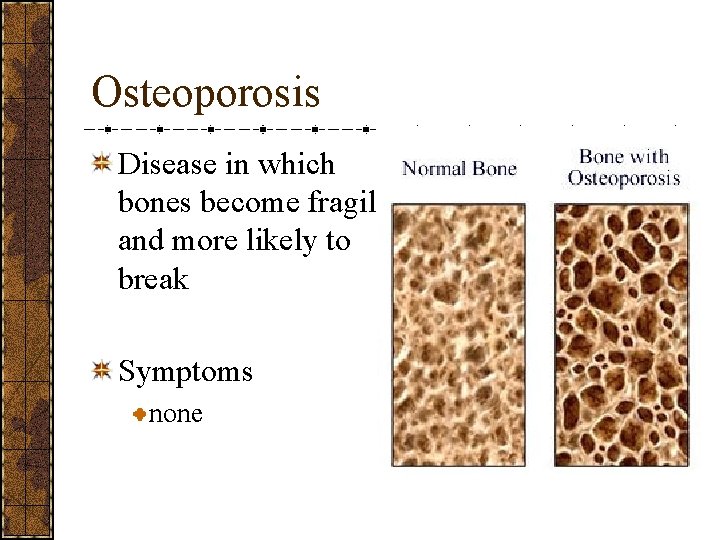

Osteoporosis Disease in which bones become fragile and more likely to break Symptoms none

Osteoporosis Detection Bone density test Treatment Calcium and vitamin D Hormone replacement therapy (HRT)